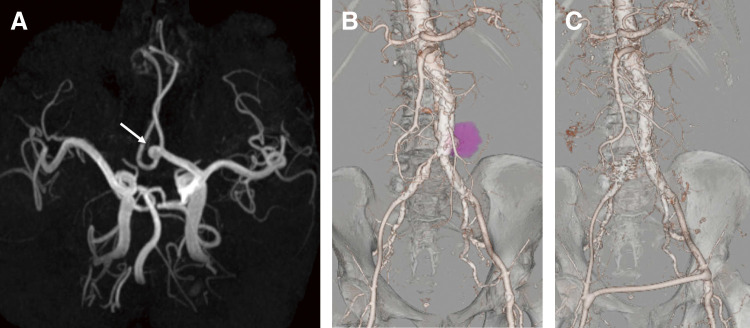

52岁男性脊柱侧凸伴寻常型银屑病,接受英夫利昔单抗治疗,表现为右侧大胃网膜动脉瘤(GEAA)。手术切除后,发现了前交通动脉和腹主动脉的其他动脉瘤。组织病理学检查显示假性动脉瘤伴组织血栓和明显的急性炎症,包括内侧壁中性粒细胞浸润。尽管培养阴性,但不能排除感染相关的血管损伤。本病例强调了慢性炎症性疾病中罕见的免疫介导的血管病理,强调了急性炎症和银屑病相关免疫失调在内脏动脉瘤形成中的潜在作用。

A 52-year-old man with scoliosis and psoriasis vulgaris, treated with infliximab, presented with a large right gastroepiploic artery aneurysm (GEAA). Following surgical resection, additional aneurysms of the anterior communicating artery and abdominal aorta were identified. Histopathological examination revealed a pseudoaneurysm with organizing thrombus and marked acute inflammation, including neutrophilic infiltration of the medial wall. Despite negative cultures, an infection-related vascular insult could not be excluded. This case highlights a rare immune-mediated vascular pathology in the context of chronic inflammatory disease, emphasizing the potential role of acute inflammation and psoriasis-associated immune dysregulation in visceral artery aneurysm formation.